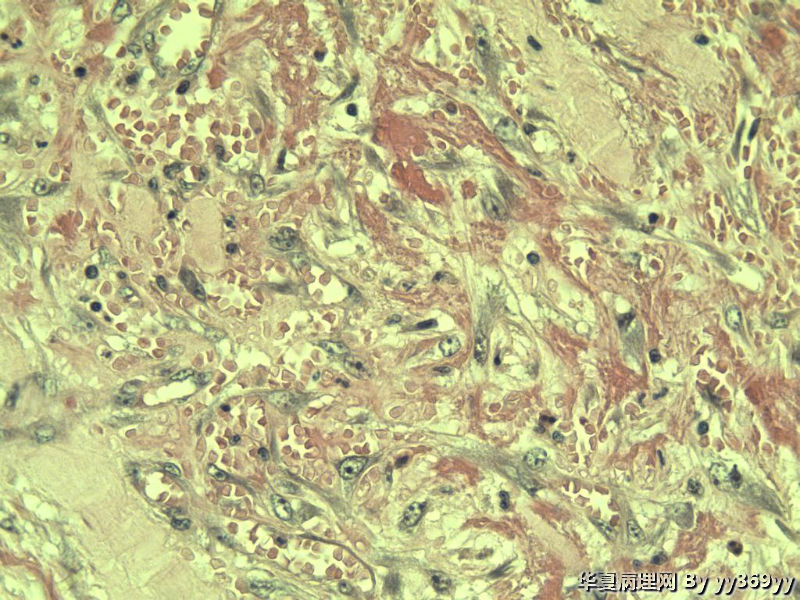

补取了几块 肌层纵行和横行平滑肌之间很多这种细胞 是什么??

名称:图1

描述:a625.Jpg

神经节细胞

这些都是增生的神经节细胞,在溃疡周围的正常粘膜里找找看有无肉芽肿

我考虑:良性病变。慢性炎性肉芽肿。有无手术史?外伤史?楼主的HE切片染色怪怪的,像发黄的老照片

考虑炎性肌纤维母细胞瘤

第一次发的图片有低倍的吗,与长肠壁关系呢?第二次发的是神经节细胞